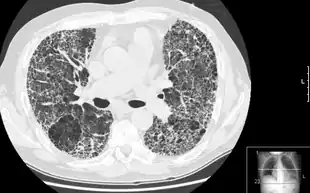

HRCT of lung showing extensive fibrosis possibly from usual interstitial pneumonitis. There is also a large emphysematous bulla. | |

HRCT is used for diagnosis and assessment of interstitial lung disease, such as pulmonary fibrosis, and other generalized lung diseases such as emphysema and bronchiectasis.

HRCT may be diagnostic for conditions such as emphysema or bronchiectasis. While HRCT may be able to identify pulmonary fibrosis, it may not always be able to further categorize the fibrosis to a specific pathological type (e.g., non-specific interstitial pneumonitis or desquamative interstitial pneumonitis). The major exception is UIP, which has very characteristic features, and may be confidently diagnosed on HRCT alone.[9]